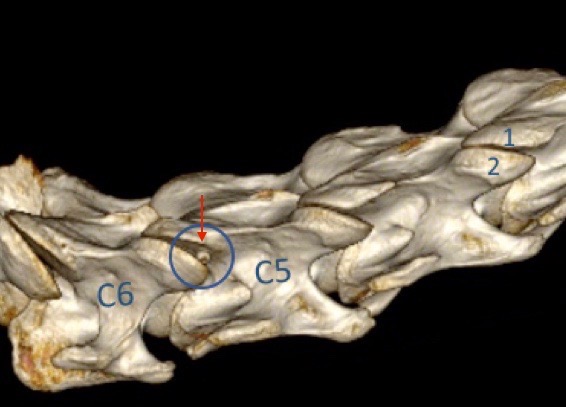

Někdy si už na základě rentgenů můžeme být skoro jisti příčinou potíží. Vždy je však nezbytné provést i myelografické vyšetření, během kterého je v celkové anestezii do epidurálního prostoru páteřního kanálu aplikována kontrastní tekutina. V místě zúžení, ve kterém dochází ke kompresi míchy, je nedostatečné množství kontrastu. Po injekci kontrastu do páteřního kanálu je provedeno CT vyšetření celého krku, jehož výsledkem je 3D obraz krční páteře, který umožní objevit nejenom dorsoventrální komprese (tlak na míchu zeshora nebo zespodu), ale také obtíže vznikající při pravolevém ohnutí krku (obr. 6).

Obrázek 6: 3D rekonstrukce (CT obrázek) OCD fragmentu v krku v oblasti meziobratlového kloubu C5–C6, úlomek byl odstraněn pomocí artroskopie